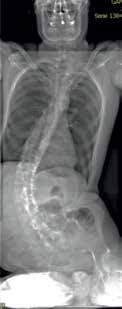

Die bildgebende Diagnostik wird bei schweren Fehlhaltungen in Betracht gezogen und mittels EOS-Röntgenbild der Wirbelsäule mit Becken und Kopf in der frontalen und sagittalen Ebene durchgeführt (Abb. 2). Die Physiotherapeuten erfassen den Muskel- und Gelenkstatus der unteren Extremitäten und die Beweglichkeit des Rumpfes und des Beckens. Gemeinsam mit den Ergotherapeuten werden die Schmerzen und die Spastizität untersucht, zudem werden Gelenkseinschränkungen und Kontrakturen gemessen.